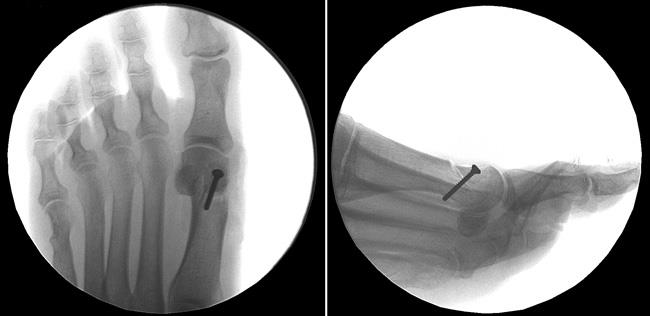

An osteotomy is a surgical procedure in which your doctor makes precise cuts in the bones to realign the joint and correct the bunion deformity. After cutting the bone, the newly adjusted position is stabilized using pins, screws, or plates. This realignment ensures the bones are straighter and the joint is properly balanced.How Osteotomy Works

Reproduced from Hirose CB, Coughlin MJ: Proximal and Distal First Metatarsal Osteotomies for Hallux Valgus, in Flatow E, Colvin AC, eds: Atlas of Essential Orthopaedic Procedures. Rosemont, IL, American Academy of Orthopaedic Surgeons, 2013, pp 535-539.